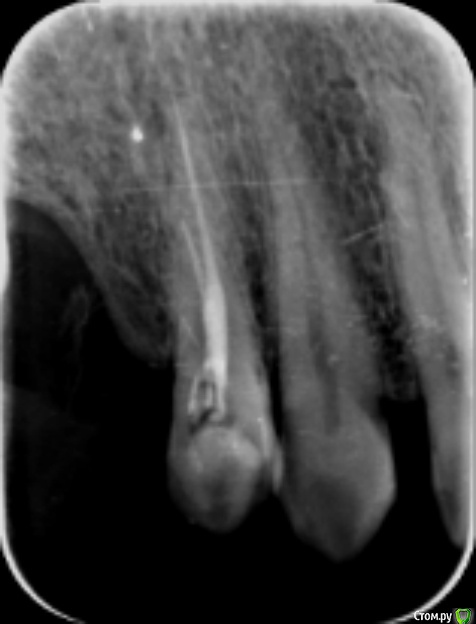

LK9722 Опубликовано 20 февраля, 2015 Поделиться Опубликовано 20 февраля, 2015 Прошу совета. Незаметно на верхних правых (по рентгену) 6 и 7 появился кариес, то есть я видел только маленькую точку на боковом торце 6-ки и тщательно чистил их, и эта точка в таком состоянии много-много лет, с 2005 или даже раньше. И вдруг безо всякой нагрузки откололся кусок верхней 7-ки, откололся настолько легко что похоже было что прогнил зуб капитально.Причем на всю толщину зуба, то есть как бы 1\5 зуба но вертикально, по самый корень. При этом до самого откалывания боли не было, и кариес был нетипичным когда сначала дырка потом болит потом только начинает разрушаться, здесь этого не было. После того как откололся кусочек я сделал орто (там видно это), но особой боли при накусывании не было и только через несколько дней после снимка вдруг появились классические признаки (похоже что дело дошло до пульпы и стало больно накусывать зубом). После этого начали его лечить и почему-то один из каналов резко отличался от двух других, т.е. сразу стало понятно что он проблемный, два канала уже на второй визит были сухие и готовые к пломбированию, а этот канал парил мозг еще около 5-6 недель, продолжал кровить и вроде бы запах показывал что там не все ОК. И чувствительность показывала что в отличие от двух других, этот канал проблемный. Вопрос, видно ли по снимку что кроме отколовшегося кусочка зуба там еще и проблемный корень ? Вообще что можете сказать про эту правую 7-ку ? Откуда пошел кариес, сверху или от корня ? Прилагаю снимки с 2011 года по декабрь 2014. Еще есть такие вопросы. 1. Зуб верхняя 6-ка имеет ли рентген-признаки кариеса ? Сейчас скоро будем ставить коронку на 7-ку и важно понять, нужно ли с заднего торца 6ки пролечить темные точки если они там найдутся ? Я вижу что на переднем торце такая точка есть много лет. Хочется решить вопрос с 6-кой прежде чем новая коронка на 7 зубе закроет доступ к торцу 6-ки. 2. Зуб 8-ка (маленький и ненужный) лучше удалить нафиг ? 3. Есть ли признаки кариеса на левой верхней 6-ке ? 4. Что скажете про импланты (про все 6 штук), и что лучше ставить на нижние импланты - сваренные вместе коронки или отдельные ? 5. Верхняя правая 4-ка с пролеченными каналами, с 2011 года при постукивании и накусывании не то чтобы болит, но немного не так себя ведет чем все остальные живые или леченые зубы. Можно сказать почти не ощутимая боль есть. Доктору я говорил что после лечения каналов чуть больно было нажимать рядом с носом (где корень заканчивается верхнего этого зуба). Прилагаю отдельный снимок этого зуба (от 2011 года). Что можно сказать про него в динамике, от 2011 до 2014 года ? Можно ли его в таком состоянии накрывать вкладкой и коронкой ? Сейчас он с пломбой с тех пор, уже более 3х лет. 6. На первом снимке виден нижний мост, который прослужил с 2004 по 2009 а потом стал болтаться на 6 зубе, проходил еще до 2013 года и наконец слетел. Выяснилось что от опорной нижней 6ки ничего не осталось, его обпилили и оставили половину. Керамика на нем начала отлетать лет через 5 почему-то на мало нагруженном зубе, на нижней 4-ке (керамика Noritake).А на болтающейся 6-ке керамика была в порядке до последнего дня. Странно... Что про этот мост скажете, нормально он пожил или маловато ? Ссылка на комментарий

LK9722 Опубликовано 20 февраля, 2015 Автор Поделиться Опубликовано 20 февраля, 2015 (изменено) фото прицельное верхней 4-ки сразу после лечения в 2011 году. Изменено 20 февраля, 2015 пользователем LK9722 Ссылка на комментарий

shishok Опубликовано 22 февраля, 2015 Поделиться Опубликовано 22 февраля, 2015 1)кариес на 27 зубе начался на задне-пришеечной поверхности(не сверху).Его видно на втором панорамном снимке.26 зуб рентгенологических признаков кариеса не имеет.2)восьмой удалить!3)по рг-снимку кариеса на 16 зубе нет,но нужно смотреть очно.4)по имплантам не подскажуя.т.к. я-терапевт.5)если 14 зуб беспокоит,то лучше перелечить.6)а 46 зуб нужно было удалять давним-давно(судя по первой ОПТГ).Вопрос о сроке службы моста на данный момент уже чисто риторический Ссылка на комментарий